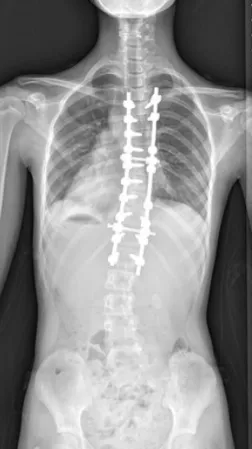

▲ 女,12岁,特发性脊柱侧凸、先天性脊柱畸形

▲ 女,14岁,青少年特发性脊柱侧凸